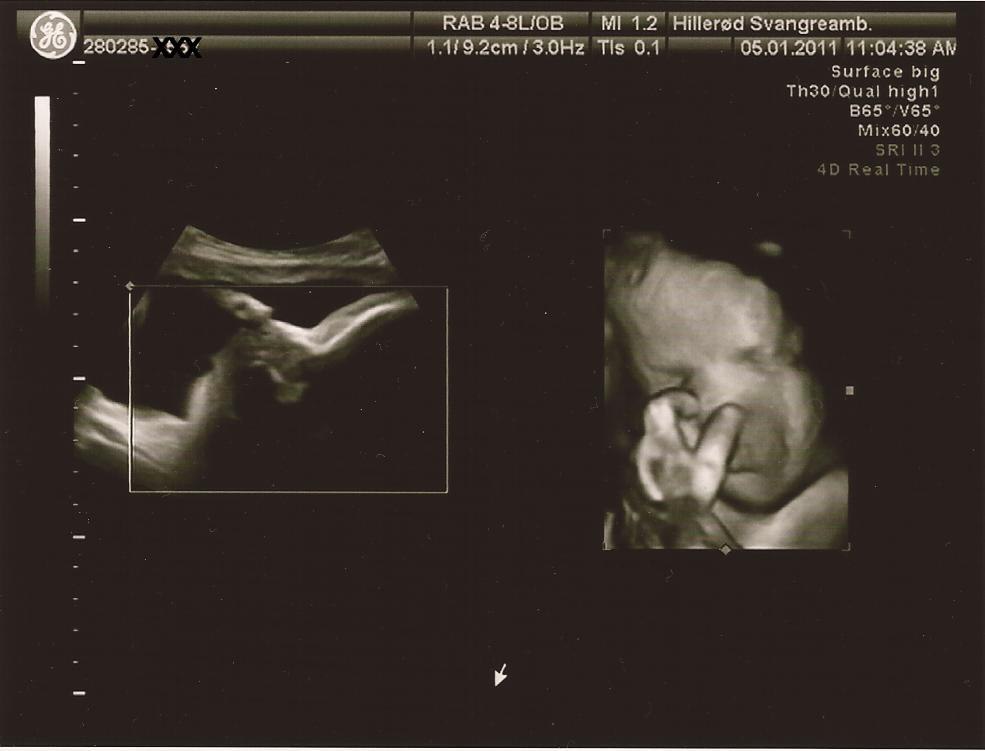

Så er der update. Der var ikke noget at være bekymret for. Med en kampvægt på anslået 2.937 gram er hun 2 % over en absolut gennemsnitsbaby på dette tidspunkt. Dejligt. Og sørme om hun ikke lige slog over i 3D, så vi kunne se at der var sul på kroppen. Det troede jeg ikke de havde mulighed for på det offentlige. Hun var ret overrasket over kvaliteten på 3D, da det normalt ikke er så godt så langt henne i graviditeten. Jeg har desværre ikke mulighed for at ligge billeder ind nu, da vores all-in-one printer er gået i stykker, men har forhåbentlig mulighed for det snart. Hun lignede forresten sin far